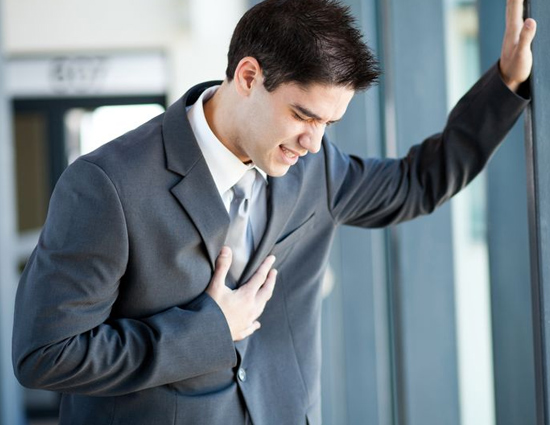

दिल में कुछ खराबी हो तो धडकनें पहले ही बता देती हैं। इसके अन्य ईशारे भी हैं, जिन्हें समझना जरूरी है। सीने में दर्द या थोडी सी मेहनत से हांफना-वैसे तो आम परेशानियां हैं, लेकिन अगर ये थोडा चलने पर, फिर बैठे-बैठे या आराम की स्थिति में भी महसूस हो तो चेतना जरूरी है। ये धमनियों में रूकावट की वजह से हो सकता है। इस पर ध्यान ना दिया जाए तो यह हार्ट अटैक जैसी जानलेवा आशंका को बढाता है। ऐसे में जरूरत है सिर्फ समय पर इसके लक्षणों को पहचानने की, ताकि उपयुक्त ईलाज कर जीवनशैली में कुछ बदलाव कर हार्ट की बिमारीयों से बचा जा सके।

जब उठे सीने में दर्द

आमतौर पर सीने में दर्द कभी भी किसी भी कारण , जैसे कि पेशियों में सिकुडन, संास नली में संक्रमण, अल्सर, एसिडिटी आदि से हो सकता है। लेकिन दर्द अगर सीने के बीचों-बीच हो और साथ में पसीना आए, धडकन बढ जाए, उल्टी आए और घबराहट या सांस लेने में दिक्कत हो तो समझ लीजिए कि डाॅक्टर को दिखाने की जरूरत है। ये लक्षण धमनियों के ब्लाॅकेज से सम्बन्धित है, जो भविष्य में हार्ट अटैक का खतरा बढाते हैं।